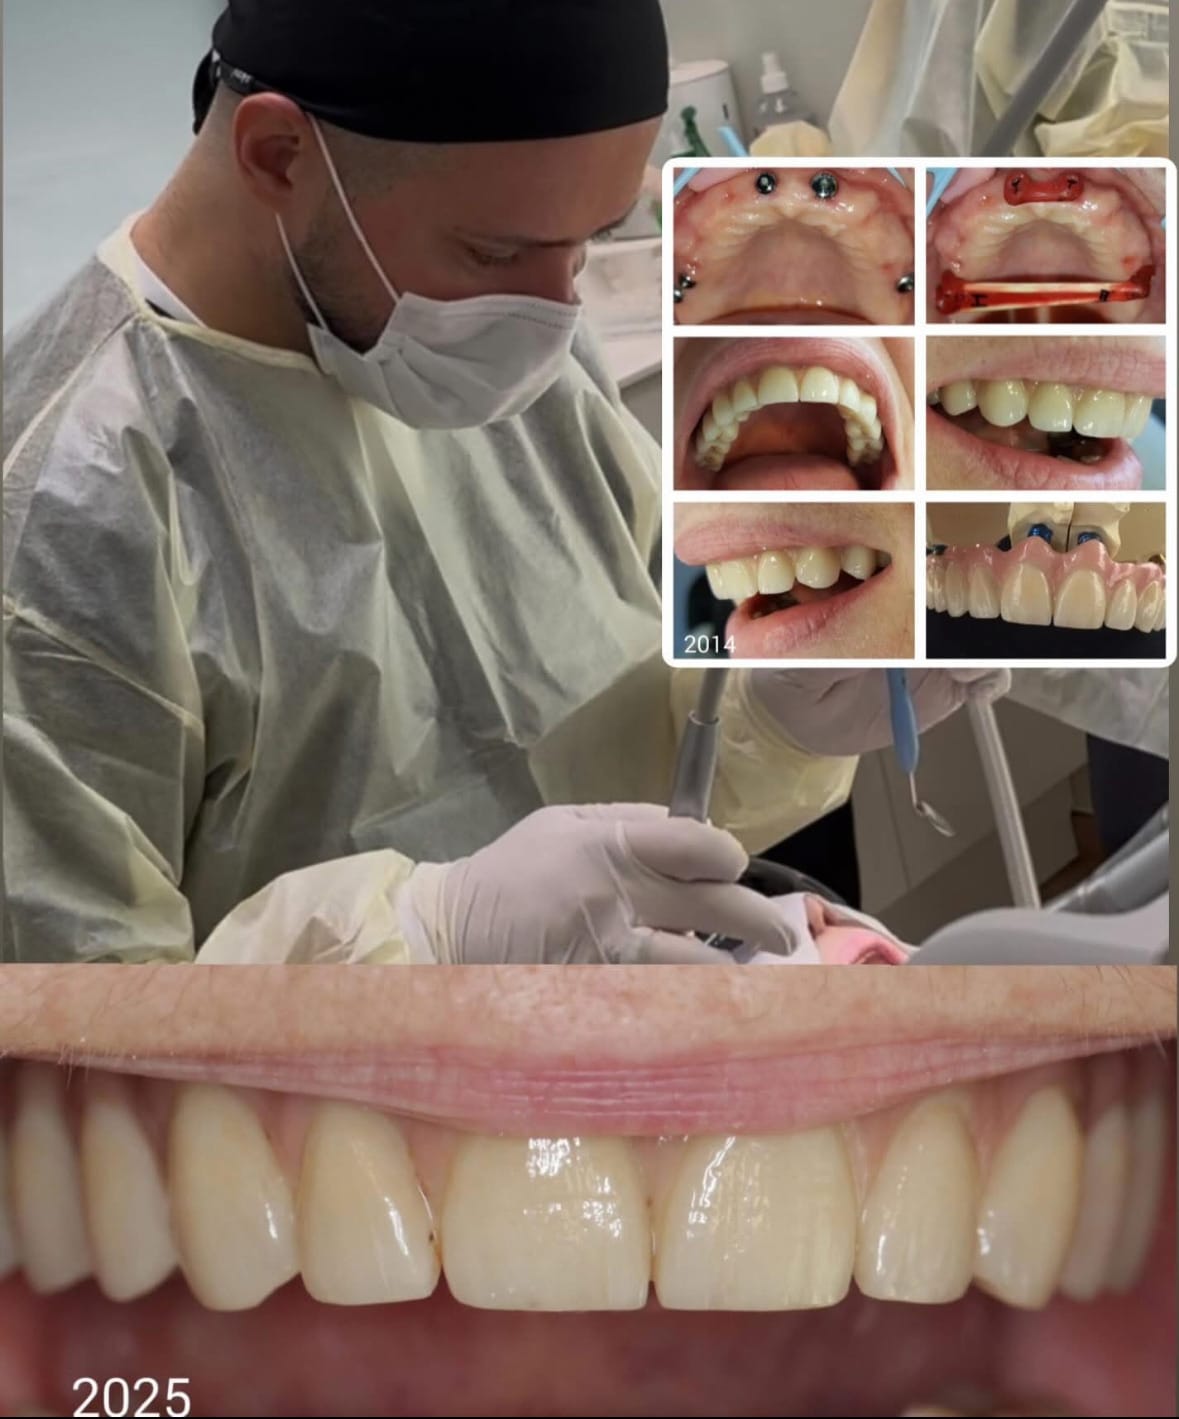

Dr Ivanovi on meedias nimetatud oma põlvkonna üheks edukaimaks hambaarstiks Eestis. Arsti hinnatusest patsientide seas räägib ilmekalt ka see, et tema käe all hoolitseb oma naeratuse eest aukartustäratav hulk tuntud muusikuid, näitlejaid, sportlasi, poliitikuid ning avalikkuse ees tuntud inimesi, kellele on väga oluline, et nende naeratus oleks täiuslikult hoolitsetud, loomulik ja enesekindlust kiirgav.

Ometi on dr Ivanovi jaoks iga patsient sama tähtis – ta usub, et iga patsient väärib enesekindlat, tervislikku ja kaunist naeratust, sõltumata sellest, kas ta astub lavale või soovib särada igapäevaelus.

Dr Ivanov on ligi kahekümneaastase kogemusega hambaarst, kelle südameasjaks on inimeste naeratuste taastamine ja hoidmine. Aastate jooksul on ta osalenud paljudes heategevuslikes telesaadetes, aidates anda tagasi enesekindluse neile, kellel see muidu ehk kaduma läinud.